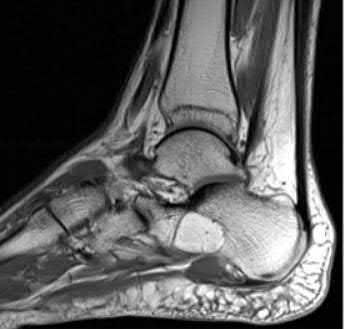

A 38-year-old male suffers the injury shown in Figure A. During operative fixation, free osteoarticular fragments are encountered and reconstruction of these pieces is attempted. Postoperatively, which of the following will have the most beneficial effect on the healing potential of the surviving chondrocytes within these reconstructed articular segments?

Figure A demonstrates a comminuted tibial plateau fracture with significant intra-articular involvement. Basic science evidence has demonstrated that post-operative gentle compressive loading may have a positive impact on articular cartilage healing; however, excessive shear loading may be detrimental.

Irrgang et al provide guidelines for rehabilitation following surgical management of articular cartilage lesions of the knee. They state that after articular cartilage repair, exercises to enhance muscle function must be done in a manner which minimizes shear loading of the joint surfaces in the area of the lesion. The authors also discuss the benefits of gentle compressive loading and motion of the joint, and its positive effects on chondrocyte nutrition.

Furthermore, they recommend a period of protected weight bearing as often being necessary, and that this should be followed by progressive loading of the joint.